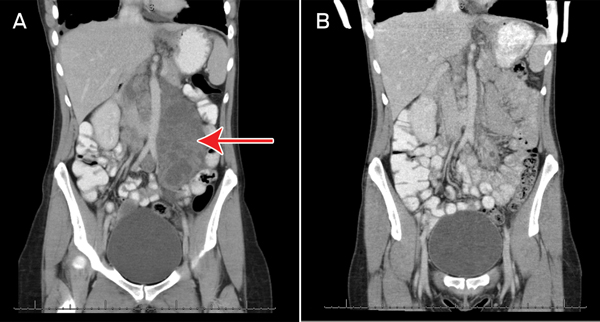

2 Abdominal computed tomography scans of Patient 1 showing (A) a baseline coronal view with a large multilobulated mass (measuring 8.3 cm × 4.3 cm axially and 17.5 cm longitudinally) in the para-aortic region (arrow), consistent with lymphangioleiomyoma; and (B) marked regression of the mass after 9 months of everolimus therapy

All five patients had significant abdominal lymphangioleiomyomas at baseline, the largest of these measuring 17.5 cm at its maximum dimension (Box 1 and Box 2). Two patients had chylous ascites at baseline. Six months after initiation of everolimus, four of the five participants had experienced significant shrinkage or complete resolution of their lymph-angioleiomyomas, and of the chylous ascites (where applicable). One woman experienced clinical resolution of her abdominal pain and distension but did not have confirmatory follow-up imaging due to financial constraints. In one woman, temporary cessation of everolimus resulted in recurrence of abdominal distension, requiring reinstitution of therapy.